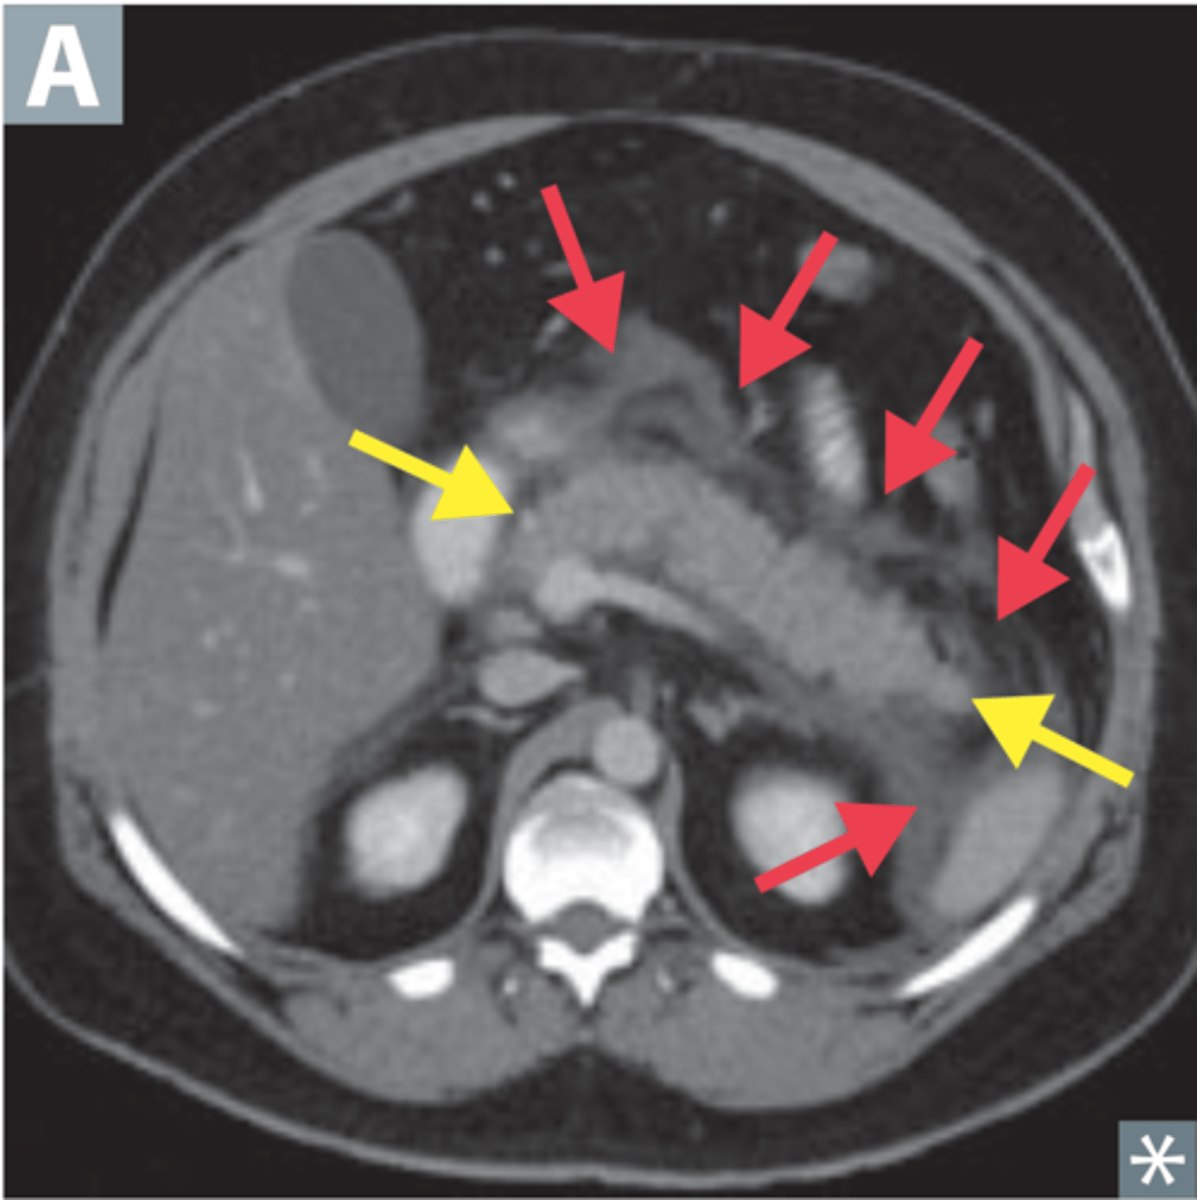

spleen

most highly vascular organ, most injured organ in blunt trauma

CT is diagnostic study of choice

Tx: mostly non-surgical

splenic laceration

hemorrhage and hematoma present, dark fluid is blood surrounding spleen